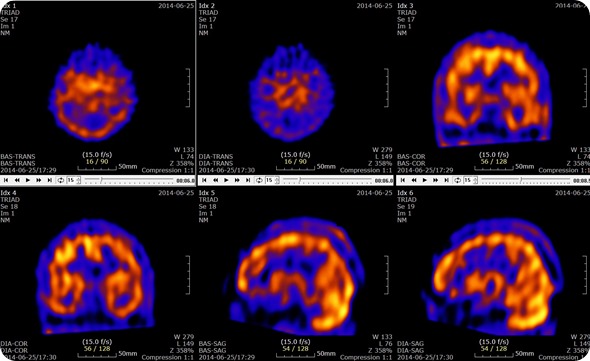

Brain SPECT with Acetazolamide Slices

Brain SPECT with Acetazolamide Slices. Credit: U2em, shared under licenses Creative Commons Attribution-Share Alike 3.0 Unported